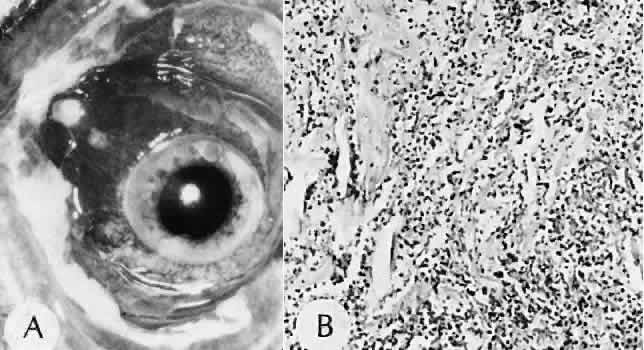

that results in reestablishment of functional ocular anatomy.1–3 The goal of therapeutic intervention in the setting of ocular trauma is to promote the repair process and to allow it to proceed as rapidly as possible and heal as completely as possible without compromising ocular function.4 CELLULAR AND EXTRACELLULAR COMPONENTS The four basic cell types found in wound healing are fibroblasts, vascular endothelial cells, inflammatory cells, and epithelial cells. Specialized cell types that participate in ocular wound healing include corneal endothelial cells, retinal pigment epithelial cells, and Müller cells of the retina. Specific cell populations enter an area of injury under the influence of complex biochemical and biophysical processes involving proteins of the extracellular matrix and the coagulation system. Intracellular proteins, such as tubulin and actin, andmyosin filaments function in cell locomotion. Extracellular matrix proteins, such as fibronectin, laminin, and type IV collagen, orient and regulate cell migration and adhesion.5 Coagulation proteins, such as von Willebrand's factor and plasminogen, alsofunction in regulating the cellular events of healing. Vascular endothelial cells are stimulated to leave their resting state and digest basement membrane, proliferate, migrate, and eventually differentiate under the direction of multiple angiogenic growth factors.6 A wound usually is filled first by a fibrin coagulum. Neutrophils, lymphocytes, and histiocytes (macrophages) enter the wound through fibrin scaffolding to clear necrotic debris and confine toxic or foreign substances. Granulation tissue often is the first type of reparative tissue in wound healing (Fig. 1). Although its composition varies somewhat, small-caliber vascular channels in a delicate collagenous stroma infiltrated by acute and chronic inflammatory cells generally characterize it. This amorphous tissue serves as a template for more definitive repair. Metaplasia is the transformation of a cell from one adult cell phenotype to a second cell phenotype. In advanced wound healing, fibroblasts acquire intracytoplasmic characteristics of smooth muscle cells (myofibroblasts).7 The myofibroblasts are able to contract and bring wound edges together. Vascular endothelial cells proliferate and migrate into the wound from preexisting adjacent vessels. The new “vessel” migrates initially as a solid bulb of endothelial cells. This solid cord of cells will canalize and differentiate into mature arterioles, venules, and capillaries. Fibroblasts grow into the wound in a radial manner but will eventually reorient and secrete collagen along lines of established tissue tension. Epithelial cells are found covering surfaces of tissue. Two distinct types of epithelial cells cover the ocular surface: corneal epithelial cells and conjunctival epithelial cells. Cell replacement is accomplished by stem cells located at the limbus for the corneal epithelium8,9 and at the mucocutaneous junction and possibly throughout the conjunctiva for the conjunctival epithelium.10 Migration and proliferation of surrounding healthy epithelial cells heal surface discontinuity. Apoptosis is a biochemical process leading to programmed cell death. Cell death in apoptosis results from intracellular messages. In necrosis, cell death results from toxic external factors (e.g., hyperosmolality). Apoptosis allows for elimination of entire populations of cells without tissue damage or an inflammatory response.11 Elimination of certain cells is advantageous in embryology (e.g., when scaffolding structures are no longer necessary as with the primary vitreous). In certain neoplastic conditions, however, defects in apoptosis may lead to disadvantageous accumulation of cells. Apoptosis also seems to be highly influential in all types of inflammation, including wound healing. In wound healing, apoptosis may function to control the type and degree of tissue response.12 In the anterior cornea, keratocytes have been observed to undergo apoptosis in response to wounding of the cornea.13,14 Abnormalities of apoptosis may be responsible for such conditions as keloid formation in the skin15 and keratoconus in the cornea.16 Wound healing of highly specialized tissues of the eye has several unique features. CORNEAL HEALING The healing of the cornea is unique relative to other soft tissues, because it lacks blood vessels and because it is lined anteriorly and posteriorly by layers of epithelial-like cells. Epithelial cells of the corneacan produce essential wound healing factors normally produced by platelets.17 Architectural repair is accomplished at the level of the corneal stroma. Abrasions are injuries generally involving only the superficial layer (epithelium) of the cornea (Fig. 2). Abrasions are commonly caused by mechanical injuries or anoxia resulting from contact lens overwear. Some or all of the layers of the surface epithelium are lost, but Bowman's membrane remains intact. After a delay of approximately 1 hour, uninjured epithelial cells at the margin of the wound loosen their intercellular and basal attachments and migrate en masse toward the injured area.18 The shape of the wound margin and the biochemical characteristics of the exposed tissue influence the direction and extent of the migration.19 If the entire corneal epithelium is abraded, migrating epithelial cells derived from the limbal stem cells are able to cover the defect completely within 48 to 72 hours. The epithelium will be much thinner than normal until mitotic division reestablishes normal thickness. Re-formation of epithelial basement membrane may not be detectable for as long as 6 weeks after injury.20 Clinically, the healed wound is transparent. Small defects of Bowman's membrane (Fig. 3) do not heal by fibrous proliferation of the stroma. The defect is filled by proliferating epithelial cells (epithelial facet formation) that reestablish the surface continuity of the cornea. The facet may be seen clinically as a focal, well-demarcated, superficial corneal opacity. A corneal foreign body causes this lesion most often. Penetrating corneal injuries involving at least one third of the stroma (Fig. 4) are covered initially by proliferating surface epithelium that may extend for a considerable distance into the stroma. The extent of corneal epithelial migration is controlled at least in part by contact inhibition of migration once contact with healthy corneal endothelial cells is established.21 Bowman's membrane has elastic properties that tend to pull the anterior margins of the wound apart. Exposure of the relatively dehydrated corneal stroma to tears and blood will cause swelling of the corneal stroma. This swelling of the stroma tends to close the wound. As the stroma heals, new collagen is produced by keratocytes or transformed monocytes. Epithelial cells will regress toward the surface. The repair collagen is different from the native collagen in size and in orientation. The healed wound is densely opaque and obvious clinically, but it may be detected histologically only by the break in Bowman's membrane. Full-thickness wounds of the cornea are associated with retraction of Descemet's membrane and separation of the posterior aspect of the wound (Figs. 5 and 6). Secondary aqueous, a proteinaceous coagulum, may seal the wound posteriorly until healthy surrounding endothelial cells can spread and migrate into the injured area. Mitotic division of the endothelial cells possibly plays an important role in younger patients but probably is not clinically significant in adults. Ultimately, migrated endothelial cells will produce a new Descemet's membrane (Fig. 7).22–25 The portions of Descemet's membrane displaced into the stroma are not resorbed, but remain as the histologic marker of the site of injury. The anterior cellular surface repair of migration and mitosis of epithelial cells is the same as that described for more superficial corneal wounds. The important exception is that with full-thickness injuries, there is a risk of surface epithelial cells migrating along the posterior surface of the cornea or the anterior surface of the iris to the trabecular meshwork. The displaced epithelial cells will cause scarring of the trabecular meshwork and secondary open-angle glaucoma. CONJUNCTIVAL HEALING Conjunctival healing differs from corneal healing because of the presence of blood vessels and a lymphatic system. The conjunctival epithelium heals by migration and mitosis.26 Conjunctival stem cells are thought to originate at the mucocutaneous junction and migrate to the fornix.27 Goblet cells are produced by epithelial progenitors and appear once conjunctival epithelial cell continuity has been reestablished.28,29 The presence of vascular tissue in the substantial propria of the conjunctiva allows for the formation of granulation tissue and scar tissue, as found in soft tissues elsewhere. SCLERAL HEALING The sclera itself does not participate directly in wound healing. Partial-thickness injuries are healed by formation of granulation tissue from the epi-scleral tissue in external wounds or from uveal tissue in internal wounds (Fig. 8). Full-thickness defects of the sclera heal by granulation tissue originating in the episcleral tissue and uveal tract. Mitomycin is used in filtering procedures specifically to prevent the formation of granulation tissue and promote establishment of an aqueous fistula.30 SURGICAL LIMBUS HEALING Currently, there is a trend for the site of the cataract wound to shift from the limbus to the peripheral cornea31 to reduce induced astigmatism32 and to shorten the natural history of cataract wound healing.33 The healing of the wound is similar to that found in central corneal incisions. Healing at the site of a limbal surgical incision involves a combination of the features of repair of the cornea, conjunctiva, and sclera (see Fig. 5). Conjunctival epithelium will heal over an area of granulation tissue originating from the substantia propria of the conjunctiva and the episclera. The granulation tissue seals the wound if the wound edges are well apposed. The remainder of the healing process is similar to the healing of an external scleral wound. Granulation tissue is not formed in the internal portion of the wound because the uveal tract is not involved. The internal wound is healed by endothelial migration and reformation of Descemet's membrane in a manner outlined above for full-thickness corneal wounds.34,35 Because of the lack of blood vessels, the rate of wound healing is slow relative to that of the skin. Whereas an injury to the skin may have regained its tensile strength in 7 to 10 days, injuries to the surgical limbus may require as long as 12 months to regain a stable tensile strength. The tissues of the wound remain structurally weaker than the surrounding uninjured tissue (Fig. 9). The healing of a clear corneal cataract incision proceeds as described above. UVEAL HEALING Wound healing of the posterior uveal tract follows the general principles for healing of vascularized tissue. The iris, however, heals differently. When the iris wound is perpendicular to its circumferential ridges, such as in a typical peripheral iridectomy or iridotomy, the cut edges pull apart. Granulation tissue does not form to close iridectomy incisions probably because of the inhibitory effect of the aqueous flowing through the opening of these small incisions. Iridotomies created by argon laser (Fig. 10) may be anatomically closed by apparent migration of iris pigment epithelium.36,37 LENS HEALING Proliferation and fibrous metaplasia of the lens capsular epithelium (Fig. 11) may close small rents through the lens capsule. After maturation of the fibrous tissue, the most superficial epithelial cells will form a new lens capsule. Most wounds to the lens, small and large, result in cataracts. Small wounds, however, may result in tiny focal opacities.38–39 Lens epithelial cells undergo fibromyoblastictransformation when stimulated by injury. The transformed cells are able to produce type I and type III collagen and glycosaminoglycans.40 This is the fundamental process resulting in opacification of the posterior lens capsule after extracapsular cataract extraction or phacoemulsification.41 Apoptosis (programmed cell death) also plays a role in the formation of secondary cataracts.42 RETINAL HEALING Wound healing of the neurosensory retina follows the principles of wound healing. There is an initial removal of all necrotic tissue by phagocytosis followed by proliferation of cells to form a chorioretinal bond. The healing, however, is modified in most instances by the lack of participation by the blood vessels.43–45 Astrocytes from the neurosensory retinaproliferate from the peripheral viable tissue into the wound and downward into the area of the subretinal space (Fig. 12). Retinal pigment epithelial cells from the peripheral viable tissue undergo fibrous metaplasia and proliferate upward into the area of the subretinal space. When the two proliferating cell types unite, a tight chorioretinal bond is formed. Increased retinal adhesiveness has been estimated to be 140% of the normal degree of adhesiveness 2 weeks after photocoagulation.46 Retinal holes may heal spontaneously if supported by an intact vitreous base or if located adjacent to the retinal pigment epithelium (Fig. 13).47,48 For the retinal pigment epithelium to differentiate, it must be in contact with overlying retinal pigment epithelium.49 Choriocapillaris repair from a photocoagulation wound of the retina appears to proceed in a manner similar to that of repair of capillary thrombosis in other tissues.50 The vascular repair process may not reproduce the lobular architecture of the native choriocapillaris.51 The choriocapillaris may regenerate in areas of restored retinal pigment epithelium.52 Proliferative vitreoretinopathy is an expression of abnormal retinal wound healing.53 Interruption of Bruch's membrane may allow the ingrowth of fibrovascular tissue from the choroid into the subretinal space, resulting in a modified granulation wound healing process and subretinal scarring.54 |